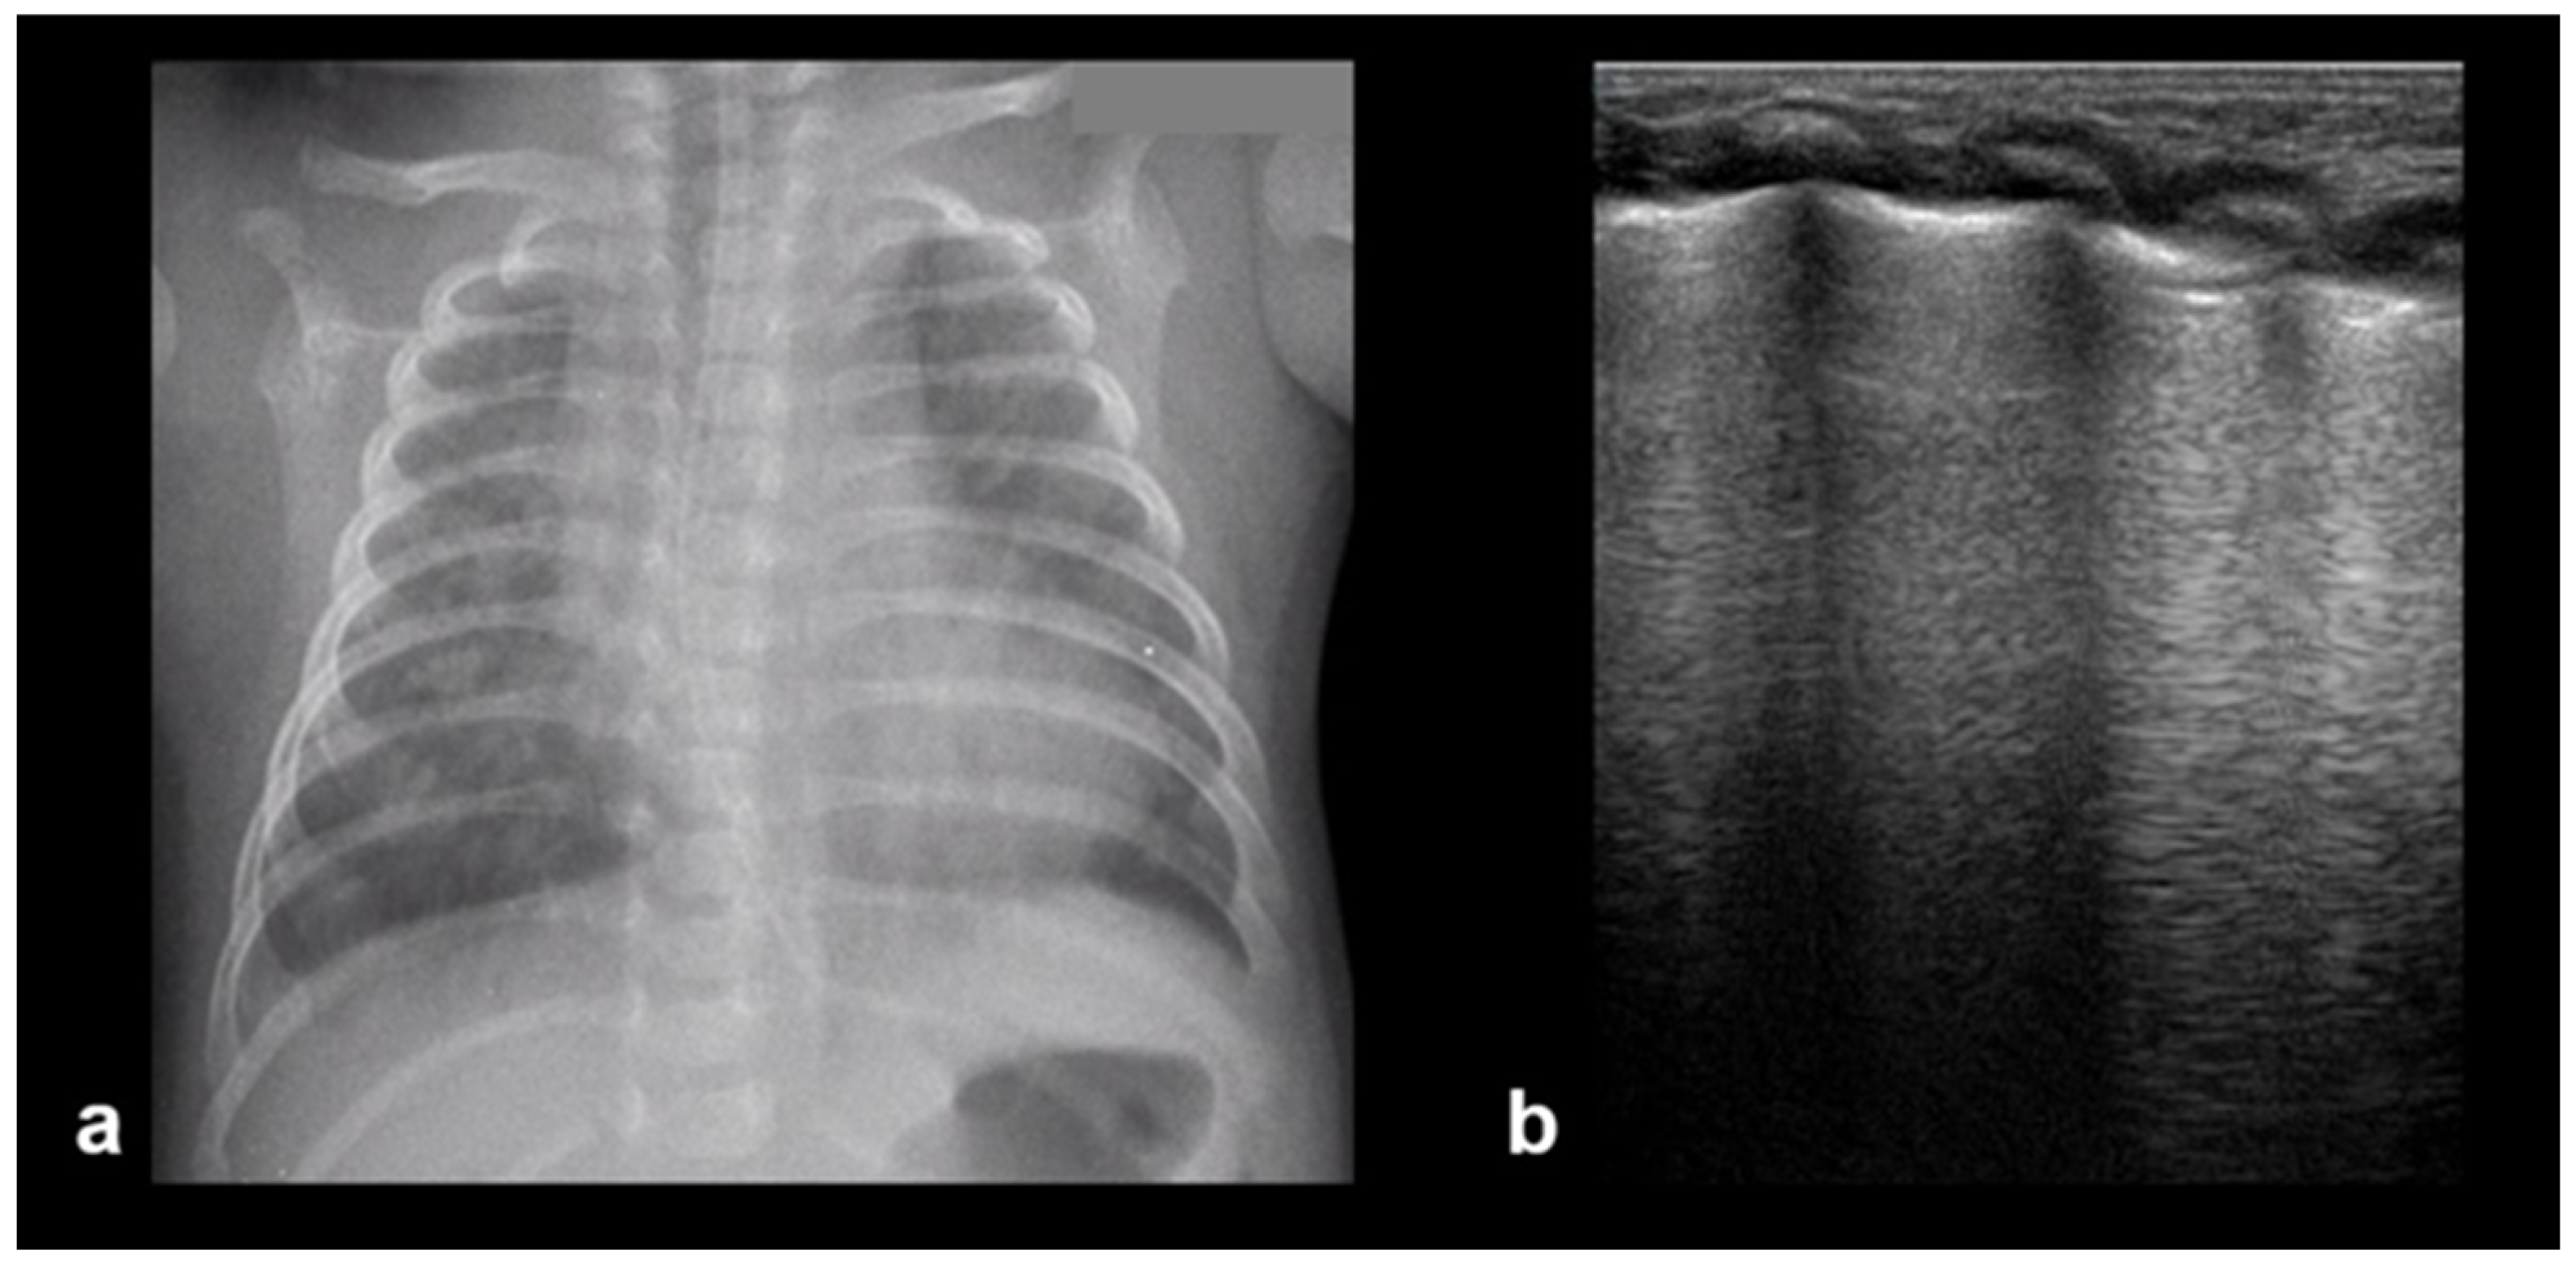

3.2.2. Transient Tachypnoea of the Newborn—Respiratory Distress Syndrome

3.2.3. Transient Tachypnoea of the Newborn (TTN)

3.2.4. Respiratory Distress Syndrome (RDS)